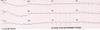

En 73-årig mand indlægges med brystsmerter af trykkende karakter gennem 2 timer. Der tages nedenstående EKG. Patienten får ingen medicin, han har tidligere røget 10 cigaretter dagligt og han er en normalvægtig. Hvad er diagnosen?

- Anteriort STEMI (ST elevations akut myokardieinfarkt)

- Inferiort STEMI

- Non-STEMI med ST segment depression

- grads AV-blok

- Perikardit med diffuse ST segment elevationer

En 73-årig mand indlægges med brystsmerter af trykkende karakter gennem 2 timer. Der tages nedenstående EKG. Patienten får ingen medicin, han har tidligere røget 10 cigaretter dagligt og han er en normalvægtig. Hvad er diagnosen?

- Anteriort STEMI (ST elevations akut myokardieinfarkt)

- Inferiort STEMI

- Non-STEMI med ST segment depression

- grads AV-blok

- Perikardit med diffuse ST segment elevationer